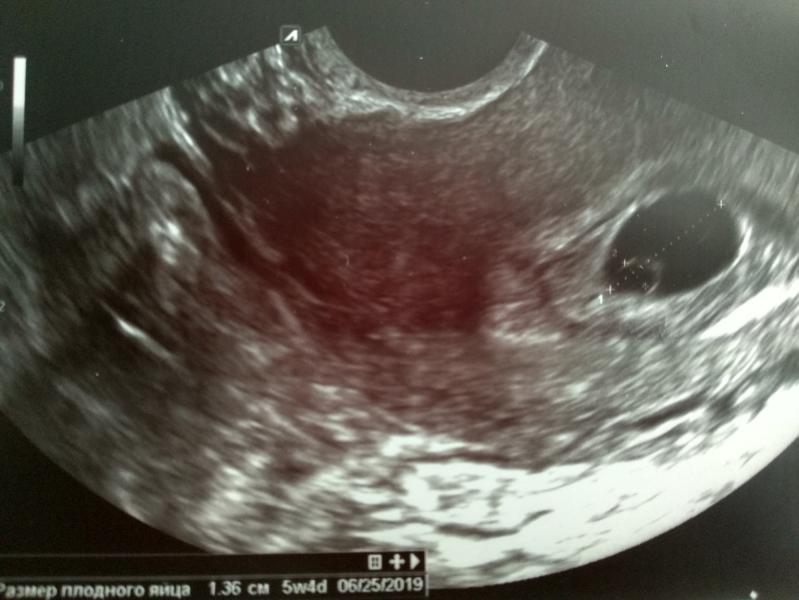

Делаем, сначала обычное, мочевой пустой. Трансвагинальное, говорит срок 5 недель. Эмбрион не визуализируется. Говорит смотреть в динамике и к врачу. Под вопросом замершая Б? Либо реально развитие на 5 недель. А к нему только 9.11. записалась на УЗИ через неделю. Я реально знаю, что зачатие было либо 19.09 либо 23.09 - это и есть 5 моих недель. Но акушерский срок же плюс две недели примерно, с первого дня последних М. Сама чувствую что все в порядке, просто мы ещё кнопочки, а муж немного в панике. Девочки, кто сталкивался? Все же хорошо будет? И ещё, и врач на осмотре и узист сказали что матка назад и сзади- что это такое? Заранее все спасибо!)

Это же нормально, что в 5 недель не видят эмбрион, плодное яйцо есть, сейчас важнее что оно там где ему положено быть. Через недели 1,5-2 повторите, если вы переливаете, в 7 уже точно виден эмбрион, и прослушиваемся сердцебиение

@v.vasilisa93 сказала узист наблюдать в динамике замершая это беременность или нет.